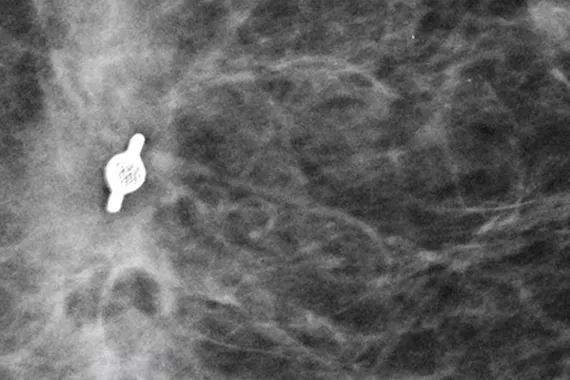

Tumark® Biopsy Site Markers

Intelligent utformade för att ge långsiktig synlighet. Alla Tumark-markörer är icke biologiskt nedbrytbara, biokompatibla permanenta markörer med utmärkt synlighet och är utformade för att minimera rörelse.1

Bildgalleri